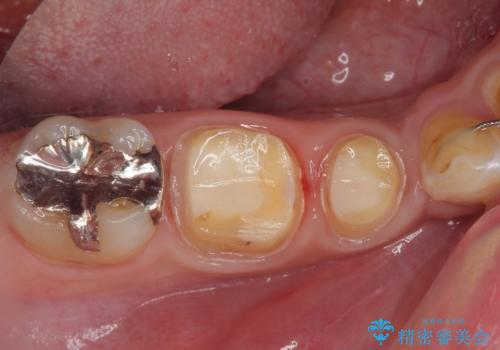

拡大鏡視野下でメタルインレー、虫歯を除去しフルジルコニアクラウンに適した形に整えました。

歯と歯茎の間に圧排糸と言われる糸を入れてシリコーン印象材にて型どりをしました。